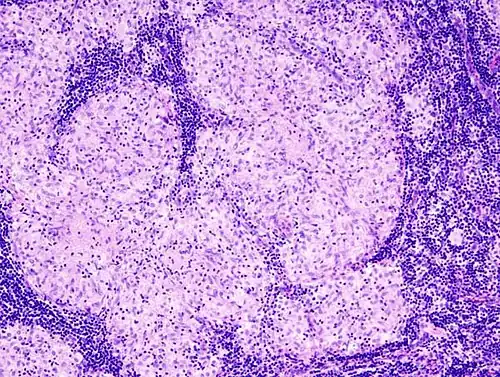

Histopathology

Sarcoidosis is characterized by the formation of non-necrotizing ("non-caseating") granulomas in various organs and tissues.[95] Giant cells, specifically Langhans giant cells, are often seen in sarcoidosis.[96] Schaumann bodies seen in sarcoidosis are calcium and protein inclusions inside of giant cells as part of a granuloma.[97] Asteroid bodies can be seen in sarcoidosis.[97] Hamazaki–Wesenberg bodies can be seen in lymph nodes and more rarely in lung biopsies with sarcoidosis and are inclusion bodies of lysosomes with protein, glycoprotein and iron.[98]

Sarcoidosis in a lymph node -